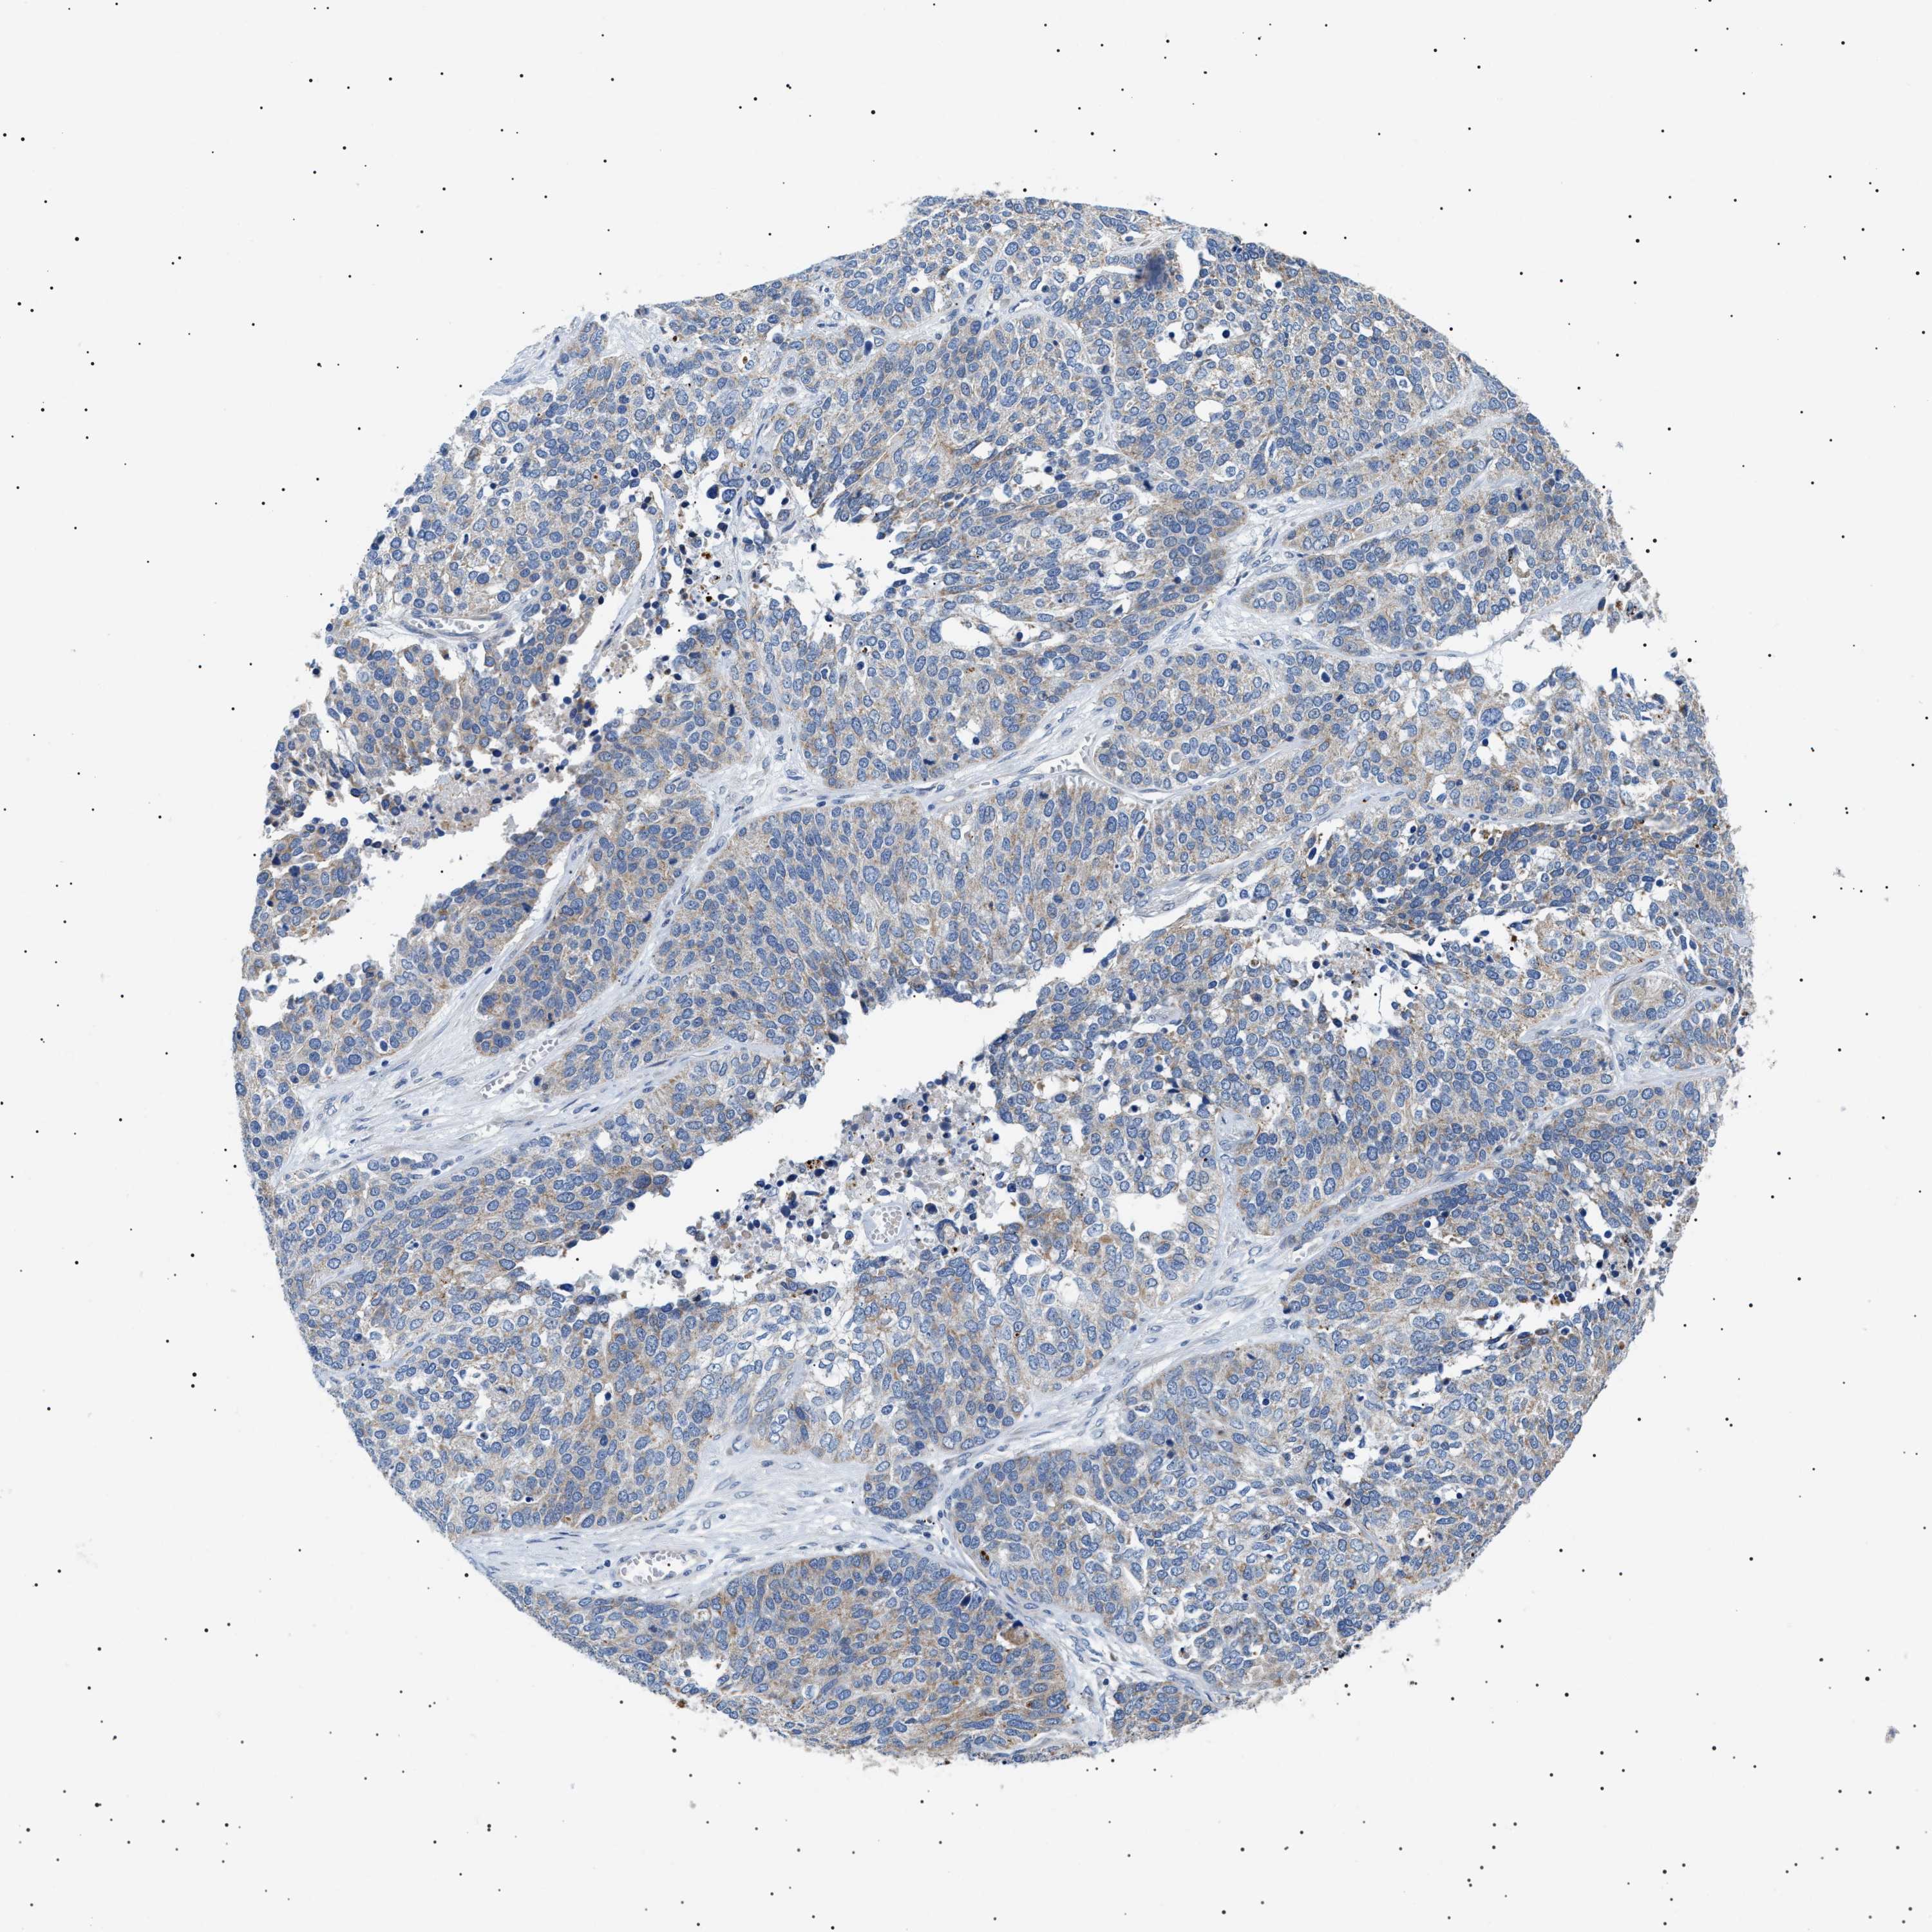

OVARIAN CANCER - Protein expressioni

A mouse-over function shows sample information and annotation data. Click on an image to view it in a full screen mode. Samples can be filtered based on level of antibody staining by selecting one or several of the following categories: high, medium, low and not detected. The assay and annotation is described here.

Note that samples used for immunohistochemistry by the Human Protein Atlas do not correspond to samples in the TCGA dataset.

Antibody stainingi

Antibody staining in the annotated cell types in the current human tissue is reported as not detected, low, medium, or high, based on conventional immunohistochemistry profiling in selected tissues. This score is based on the combination of the staining intensity and fraction of stained cells.

Each image is clickable and will lead to virtual microscopy that enables deeper exploration of all samples and also displays staining intensity scores, fraction scores and subcellular localization as well as patient and tissue information for each sample.

Antibody HPA016579

Antibody HPA059374

Cystadenocarcinoma, serous, NOS

Carcinoma, endometroid

Cystadenocarcinoma, mucinous, NOS

Carcinoma, NOS